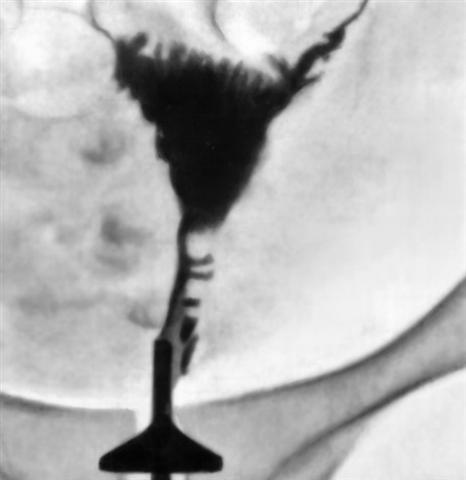

Рис. 10. Гистероцервикограмма при раке тела матки, занимающем всю ее полость и канал шейки матки.